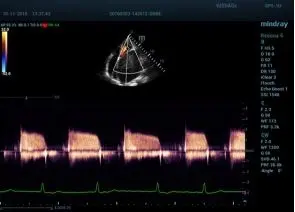

- Расширенный кардиопакет, в том числе Strain (пакет для количественной оценки движения и деформации миокарда)

Echo Boost™ режим улучшенной визуализации для кардиологии